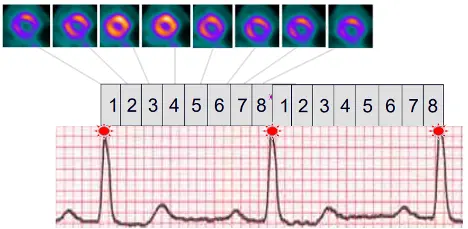

- Gated (ECG)

- Often you’ll see 8 or 16 bins between R-R intervals. We can go to the end-diastolic frame and calculate EDV and the end-systolic frame (e.g. frame 4 in example below) and calculate ESV → use ESV and EDV to calculate EF for these patients.

-1753742216064.webp)